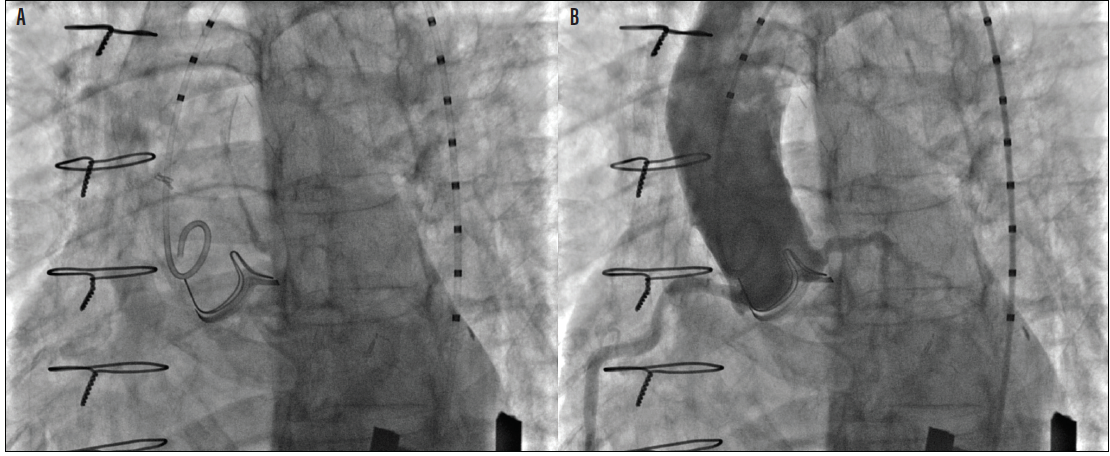

Figure 1. Patient with a failed Magna Ease pericardial valve (Edwards Lifesciences) and severely calcified ascending aorta (A). Aortogram with 1:2 orientation of the surgical valve struts, showing a low left main ostium (B).

Dr. Cheung: I think all ViVs should go through the same evaluation process, specifically in terms of preoperative imaging. This preoperative imaging should include an aortogram to assess coronary flow and potential obstruction (Figure 1). Additionally, all patients should undergo a CT scan of their aortic root to measure the height of the left coronary artery (Figure 2), the height of the right coronary artery in relationship to the surgical valve, and also the virtual transcatheter heart valve (THV) to coronary (VTC) distance, the sinotubular junction, and also to the aortic wall and it is important to know whether the sinus is large enough to accommodate the expansion of the surgical valve (Figure 2).1,2

As a result, there is a need to modulate that leaflet, which brought about the BASILICA technique. The BASILICA technique is a result of understanding that the mechanism of obstruction is mainly the leaflet of the failed valve and the need to modulate that leaflet in order to prevent obstruction (Figure 1). It was first performed in 2017 at the University of Washington by myself, and was brought about through collaboration with a team at the National Heart, Lung, and Blood Institute led by Robert Lederman, MD.